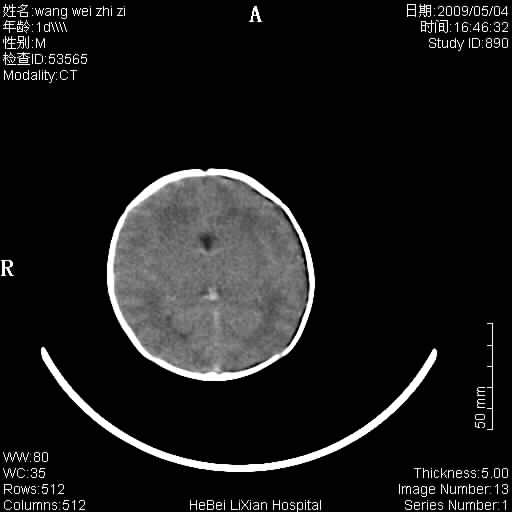

患者,男,1天,上肢抽动数次伴气促.有急产史.可以诊断珠网膜下腔出血吗?

局部5毫米薄层扫描

缺血缺氧性脑病,蛛网膜下腔出血。

此例符合缺血缺氧性脑病并蛛网膜下腔出血.